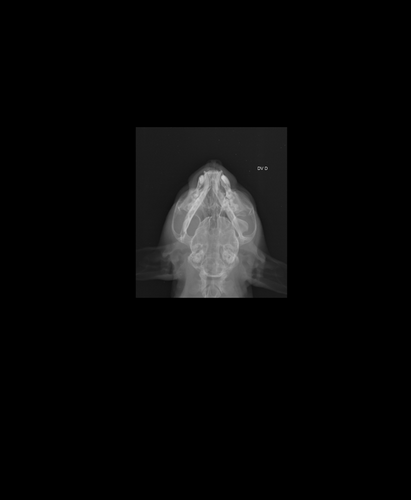

Oi eu sou a Liu, criei essa vakinha pra poder operar o meu filho peludo de nome Nego, ele é um gatinho lindo e muito dócil, adora dormir na janela e isso infelizmente causou um acidente horrível, nós temos tela de proteção em todas as janelas porém no domingo as 20:30 enquanto ele dormia na janela uma corda da tela arrebentou e ele caiu da janela do 5° andar, foram muitos metros de queda e ele acabou fraturando a mandíbula, já gastei tudo com a internação e exames mas os veterinários dizem que ele tem que se operar com urgência pra poder se alimentar e parar de sentir dor, qualquer ajuda é bem vinda e serei extremamente grata a todos, segue em anexo o que preciso para realizar a cirurgia e as radiografias do crânio dele.